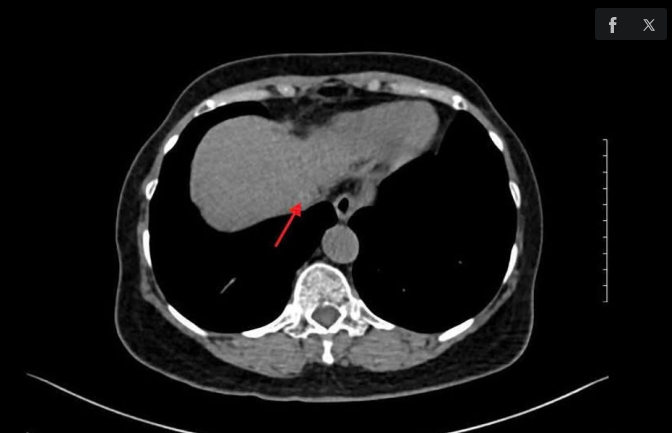

ThS.BS.CKII Lê Thanh Quỳnh Ngân, Trưởng khoa Nội tiêu hóa, cho biết chỉ số AFP càng cao, khả năng ung thư gan càng lớn. Để khẳng định, bác sĩ chỉ định chụp CT tầm soát ung thư gan, kết quả cho thấy khối u khoảng 0,5 cm, mức LI-RADS 5 (hệ thống đánh giá các khối u biểu mô gan) chẩn đoán ung thư biểu mô tế bào gan. Viêm gan C mạn tính có nguy cơ cao tiến triển xơ gan và ung thư gan. "Bà Bình là trường hợp điển hình bị viêm gan C không được phát hiện điều trị kịp thời dẫn đến xơ gan, ung thư gan", bác sĩ Ngân nói.

Kết quả chụp MRI ghi nhận bà Bình có u gan. Ảnh: Bệnh viện Đa khoa Tâm Anh